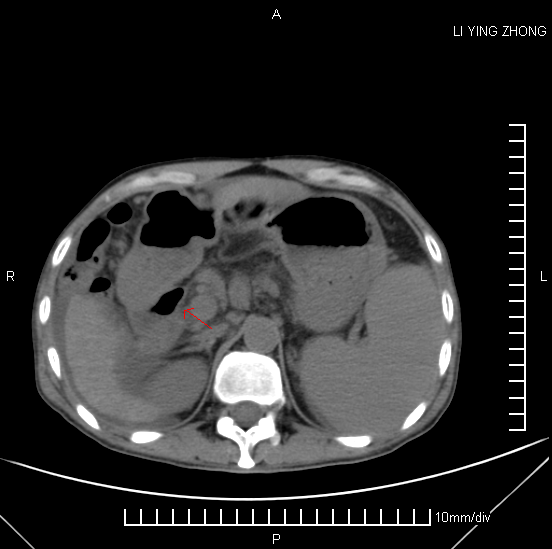

CT51135:请会诊,是否是腹腔游离气体?? ...

CT51135:请会诊,是否是腹腔游离气体??

男性,50岁,肝硬化腹水,突发腹痛、全腹压痛反跳痛明显,查血提示有败血症。请教各位红色箭头部位是否是腹腔游离气体?

考虑肝硬化、脾大、腹水,左下腹前壁见钙化,结合临床。

不是,是肠道气体